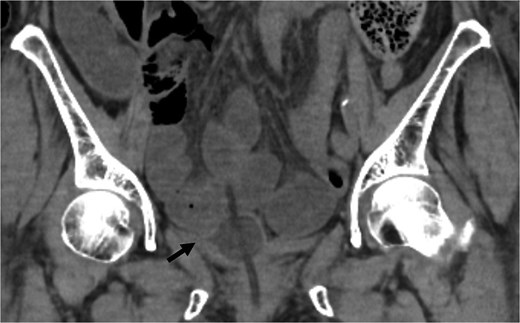

Coronal CT showed the urinary catheter was mispositioned outside the bladder (arrow).

The diagnosis of bladder rupture can be particularly challenging in cases with atypical presentations. In this patient, the presence of intra-abdominal air initially led to the suspicion of gastrointestinal perforation, although the mild abdominal tenderness was atypical for this condition. Retrospective analysis revealed that the urinary catheter had been mispositioned outside the bladder after penetrating the bladder wall, further complicating the clinical picture. This highlights the importance of considering bladder rupture in the differential diagnosis of patients with a history of pelvic irradiation presenting with intra-abdominal air and nonspecific symptoms.